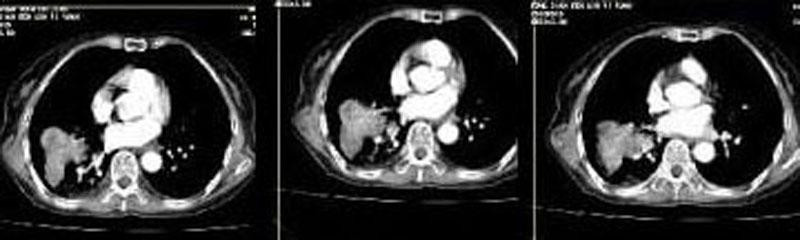

考虑右肺下叶周围型肺癌并阻塞性肺炎。

考虑右肺下叶周围型肺癌并阻塞性肺炎

考虑右肺下叶周围型肺癌并阻塞性肺炎。建议查痰、肿瘤标记物或活检。